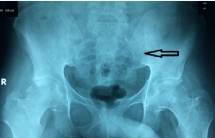

Thầy lang bắt nằm bất động 6 tháng, nam thanh niên suýt bị liệt

Được chẩn đoán đau thần kinh tọa, thoát vị đĩa đệm cột sống thắt lưng, nam thanh niên không điều trị liên tục mà đến thầy lang nằm bất động, kéo giãn tứ chi.